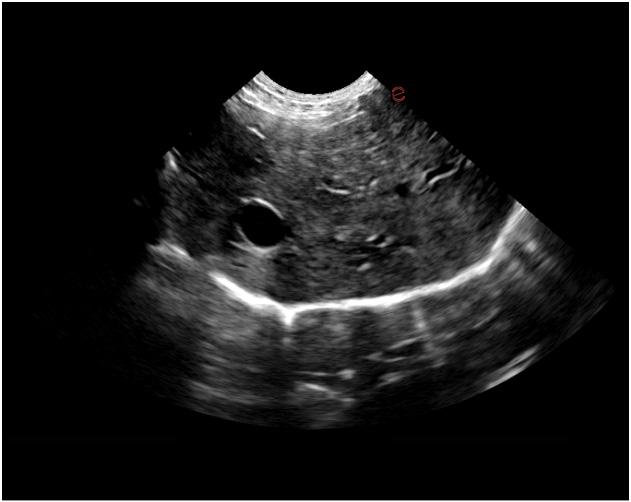

Esaote Q7 Vet er et trådløst, håndholdt ultralydapparat dedikert for veterinærer. Spesialtilpassete forhåndsinnstillinger og software og database designet for dyr. Esaote Q7 kombinerer kraften til moderne ultralydteknologi med brukervennlighet og mobilitet.

Med håndholdt ultralyd og en smartmobil/nettbrett, kan du gjøre raske og gode undersøkelser med Esaote Q7. Dets trådløse design gjør det mulig å utføre ultralydundersøkelser av høy kvalitet når som helst og hvor som helst. Alt er tilrettelagt for en vellykket undersøkelse.